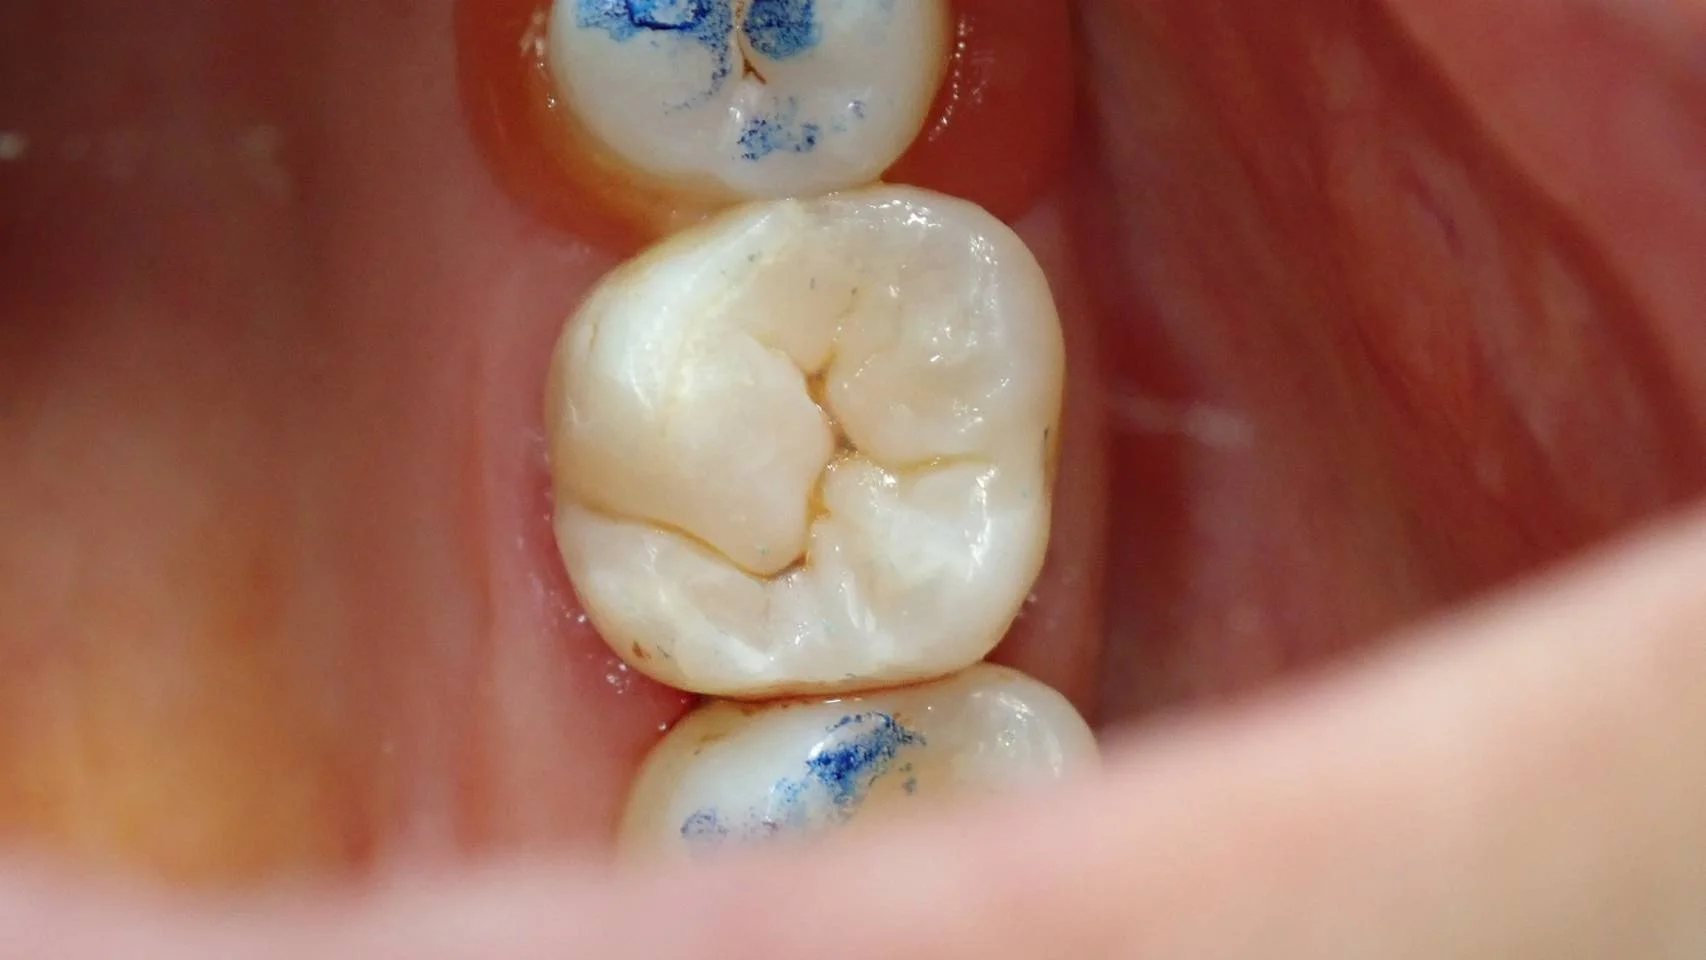

で、こちらが咬合調整後の画像です。

ダイレクトボンディング⑤|坂寄歯科医院(取手市藤代) - 画像2